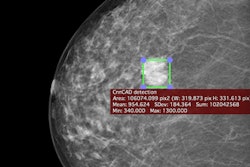

Can computer-aided detection (CAD) software based on a deep-learning algorithm accurately detect as well as characterize lesions on mammography studies? Yes, it can, according to Hungarian researchers.

In an article published online in Scientific Reports, the researchers shared how their deep-learning algorithm was able to take second place in a large artificial intelligence (AI) challenge aimed at improving risk stratification in screening mammograms. The algorithm performed even better in testing on a different database, yielding 90% sensitivity on a per-lesion basis and only 0.3 false-positive marks per image. Click here for all the details.